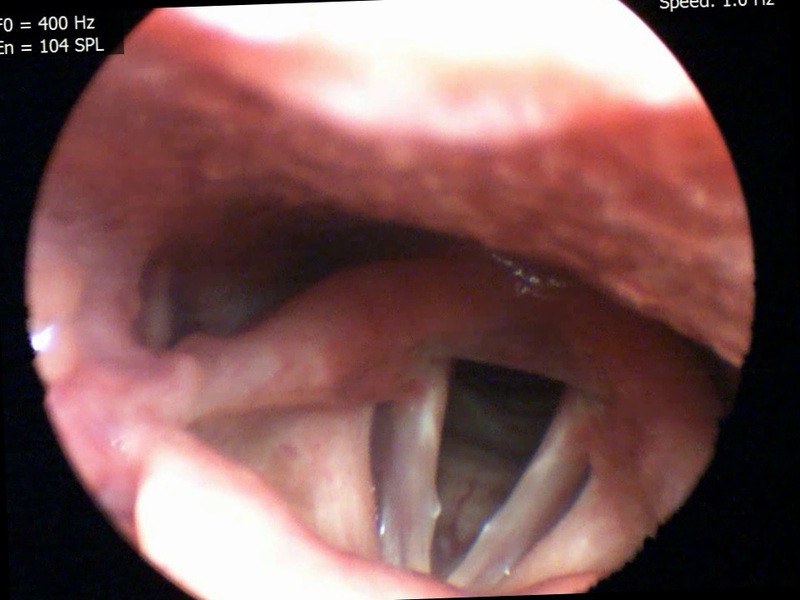

Photo H1 shows a laryngoscopy of a lesion before treatment and Photo H2 shows a laryngoscopy of the same patient after treatment.

In lesions of the vocal folds, such as those described above, excellent results are obtained in association with speech therapy. The cranial nerves that innervate the intrinsic laryngeal muscles are stimulated in order to maintain a correct tone, the production of endogenous cortisol is increased for anti-inflammatory purposes, and a regular vibration of the vocal folds is achieved through stimulation of the epiphysis.

The suggested strategy consists of 1 Cosmonauts + 2 Deep throat + 3 Corpus Callosum + 4 Synthesis Point. Corpum Callosum is required to improve coordination of the entire larynx movement and not just the one of the two true vocal folds [8].

Photo H shows a different strategy proposed for the same problem: